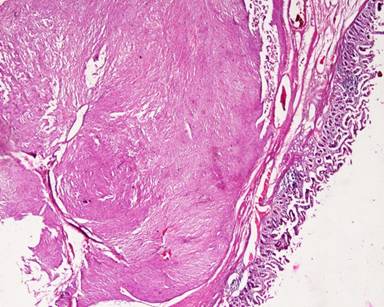

A thirty-year-old man presented with the chief complaint of mass in the right upper abdomen since one and half year. It was gradually increasing in size and was associated with occasional upper abdominal pain. Pain was dull in nature, non-radiating with no specific aggravating and relieving factor. There was history of incomplete bowel evacuation sensation and increased frequency of defecation. There was no history of vomiting, gastrointestinal bleed, jaundice, anorexia and weight loss. On physical examination, there was no pallor, jaundice and lymphadenopathy. A large firm mass about 15x10 cm extending into epigastrium, umbilical and right hypochondrium on per abdomen examination. It had round shape, bosselated surface, smooth margins, and was mobile in the transverse direction. There was no abnormality on digital rectal examination and proctoscopy. Routine laboratory tests were within normal limits. Ultrasound abdomen showed 15x10 cm heterogeneous mass in the umbilical region displacing the adjoining gut loops with no invasion. CECT abdomen showed 15x10 cm size, well defined mass with heterogeneous density in the retroperitoneum extending from pancreas to pelvic brim. It had enhancing peripheral component and non-enhancing (necrotic) central component (Figure 1). Fine needle aspiration cytology of mass smear showed blood only. On exploratory laparotomy there was large hyper vascular mass protruding through the transverse colon mesentery. Mass appeared to be originating from the anterior surface of head of pancreas. It was attached to the whole length of anterior surface of pancreas and macroscopically was not attached with the duodenum except for about one or two cm near the lower end of second part of duodenum (Figure 2). There was no metastasis in liver or peritoneum. Pancreaticoduodenectomy was done. Histopathology showed spindle cell tumor with palisading pattern and foci of necrosis (Figure 3). The mitotic count was up to 15/50 HPF. Tumor was involving duodenal muscularis propria with no infiltration in the duodenal epithelial layer and the pancreas (Figure 4). Immunohistochemical study revealed positive staining for CD117, CD34, vimentin, smooth muscle actin, and negative staining for desmin and CD31 (Figure 5). Based on these findings, the tumor was finally diagnosed as gastrointestinal stromal tumor (GIST) arising from the duodenal wall, growing exophytically and attached with the pancreas without infiltrating the pancreas. Post-operatively patient had biliary leak which was managed conservatively and discharged in satisfactory condition with the advice to take imatinib 400 mg daily.

Figure 3. Histopathology showing spindle shaped tumor arranged in palisading pattern (H&E stain, 200x). |